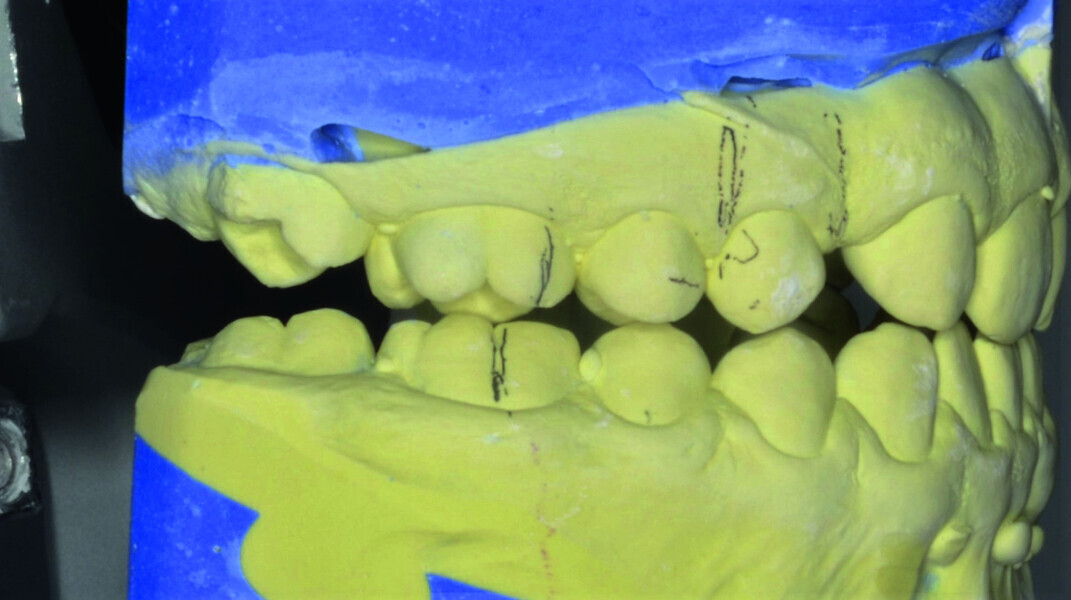

Orthodontic management of maxillary lateral incisors agenesis